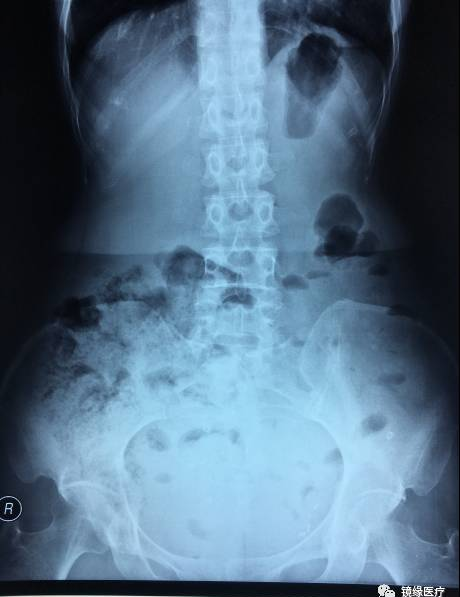

前不久,北京大学第一医院接诊一名患者,女性,55岁,便秘6年余,间断腹痛、腹胀4年余。为明确患者便秘发病原因,给予结肠传输试验检查,使用的标记物为美国Konsyl公司生产的胃肠动力标记物胶囊(润舒达)。

患者检查当天口服一粒O环型胶囊,于48h后拍摄X光片一张,检查结果如图:

根据上图所示,我们可以计算出该患者的传输指数TI=12/12=1,由此我们可以诊断该患者为排便障碍型便秘。